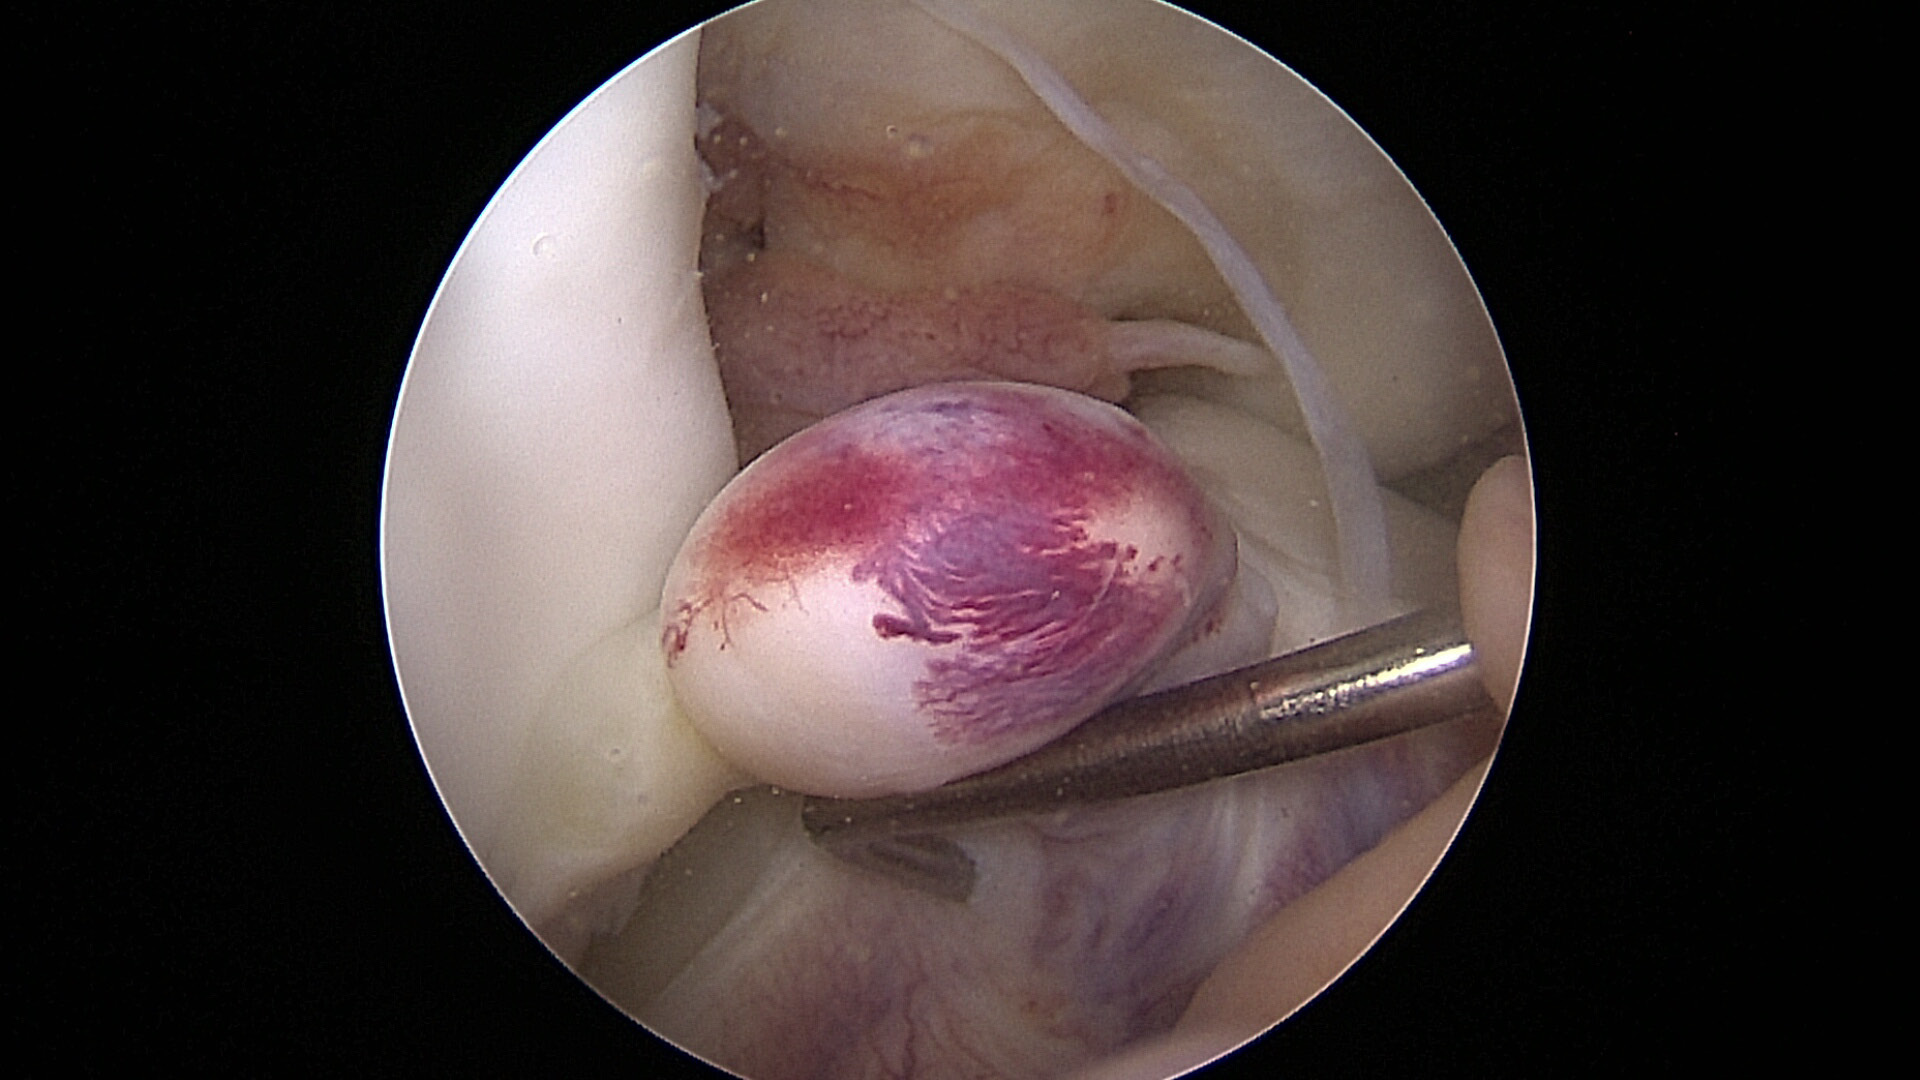

All the patients were operated on by the same team, using the same surgical technique and Neoligaments (Neoligaments) (Figure 1) or FiberTape (Biomet) (Figure 2) graft. It was fixed using Endobutton (Smith-Nephew, Watford, UK) on the femur and the interference screw, ComposiTCP30 (Biomet), on the tibia. It was prepared using the “outside-in” technique with the aimer device (Figure 3, Figure 4, Figure 5, Figure 6, Figure 7, Figure 8).